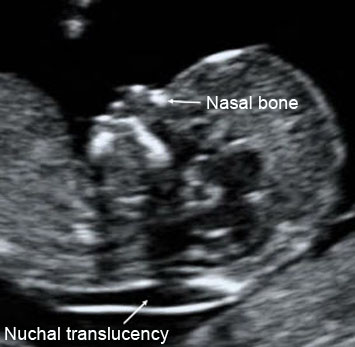

The Sonographer will measure the "nuchal fold" or "nuchal translucency". This is the fluid in the skin at the back of the baby's neck.. This fluid may be increased in babies with Down's syndrome or other genetic problem. If the nuchal translucency scan is abnormal, a referral to a Consultant in Fetal Medicine will be made and they will endeavour to see you on the day of your scan. You may be offered a definitive diagnostic test, amniocentesis, if the scan is abnormal.